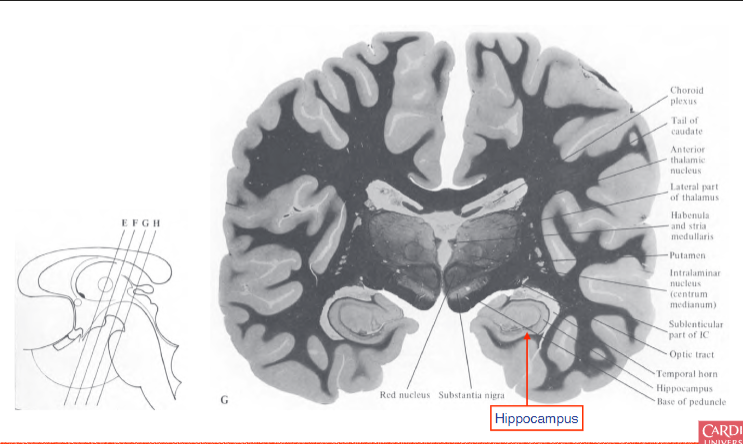

describe the hippocampus?

found posteriorly to the amygdala, involved in encoding declarative memories

describe the location of the dentate gyrus.

connected to hippocampal formation